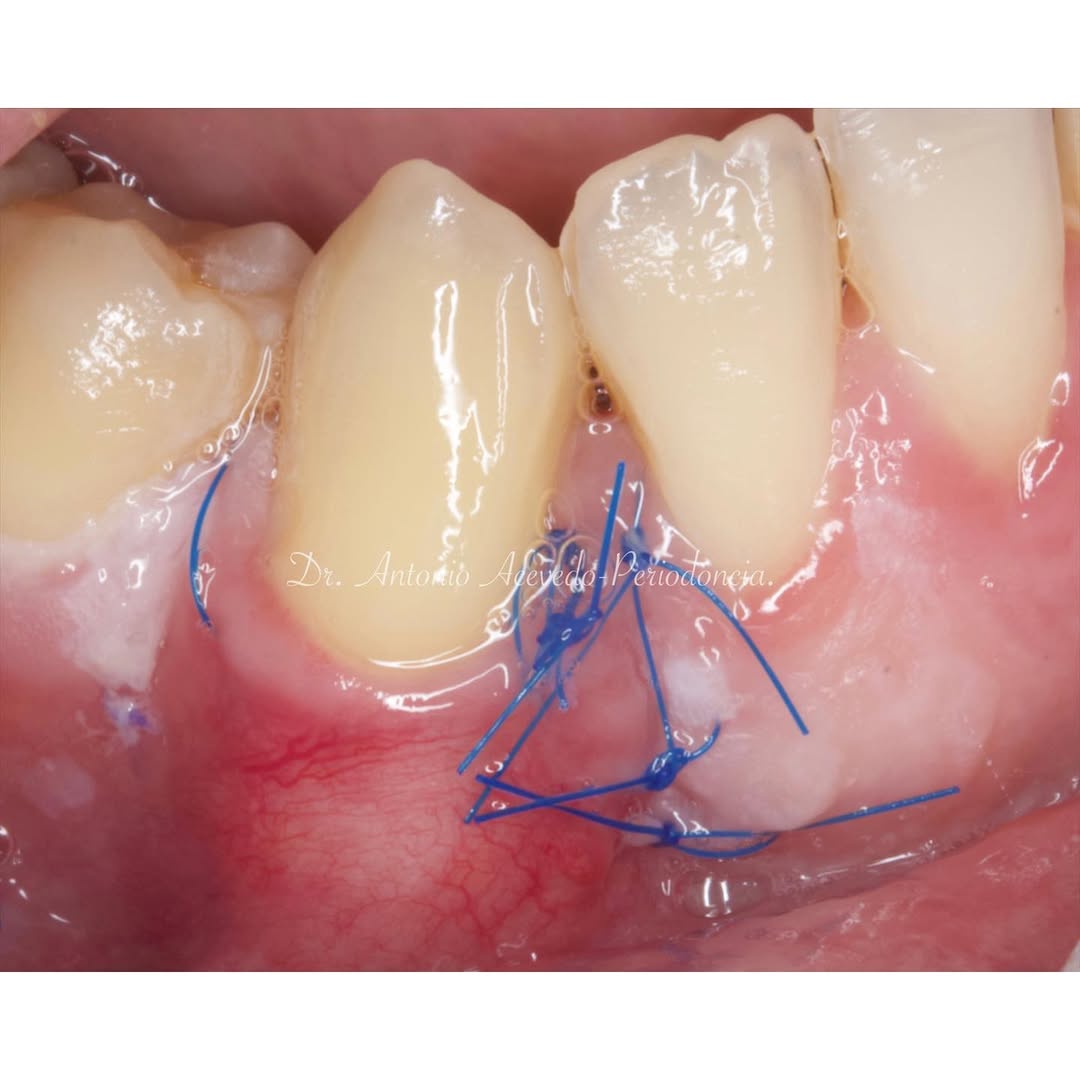

Una estancia clínica pensada para quienes quieran iniciarse o dar un paso más en el campo de la cirugía mucogingival. Durante esta experiencia tendrás la oportunidad de aprender en directo cómo se planifica y se lleva a cabo una cirugía mucogingival mediante técnica de Túnel.

La sesión

Podrás asistir a la planificación de casos y cirugía de injerto de tejido conectivo. Factores determinantes y elección de la técnica adecuada. Sumérgete en un protocolo predecible y técnicamente correcto para obtener resultados óptimos.